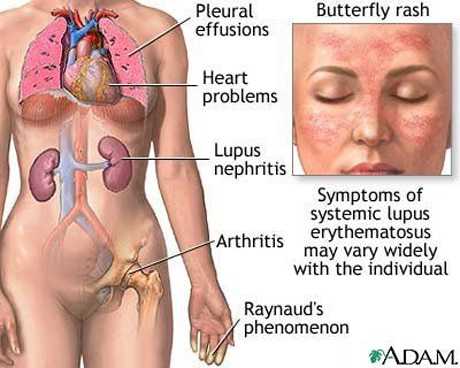

- Enfermedades